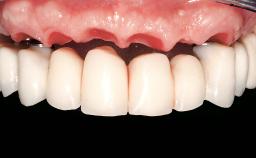

In this video Dr. Nikos Mattheos demonstrates the full diagnostic, planning and treatment sequence of an immediate implant with an immediate prefabricated provisional restoration in the esthetic zone. A 28 years old female patient presents with discoloration and increasing mobility of tooth 11. Advanced stage of external resorption is diagnosed. Patient's high esthetic demands combined with intact gingival architecture and periodontal health makes her a good candidate for immediate placement and restoration to preserve the gingival contour. Surgical and restorative treatment is planned with digital workflow based on data from CBCT and intraoral scan. An immediate temporary crown is manufactured for placement at the day of the surgery. Flapless extraction is performed, and the implant placed with guided surgery. Consequently, the buccal gap of the socket is augmented with Xenograft, while the soft tissue space maintained with a collagen plug. Finally, a provisional crown is immediately placed on the implant with a titanium temporary abutment and an emax prefabricated crown.

Biological Screw-retained restorations with appropriate contours

Prosthetic volume Adequate. Space available for ideal anatomy of the restoration

Inter-occlusal space Adequate. Capable to create an anatomically & functionally correct planned restoration

Volume and characteristics of the edentulous ridge (fixed) Adequate. No adjunctive therapy or prosthetic soft tissue replacement will be necessary

Loading Protocol Immediate

Implant-supported provisional restoration Required, elevated esthetic and/or functional demands